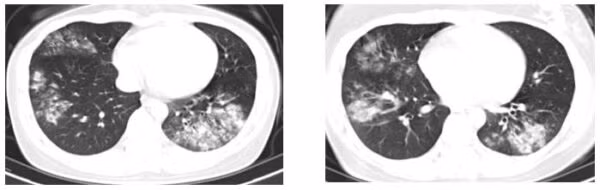

Mới đây nhất là trường hợp người bệnh nữ 34 tuổi, tiền sử khỏe mạnh, không mắc bệnh lý mạn tính, vào viện vì ho khạc đờm, sốt, khó thở. Người bệnh tự dùng kháng sinh đường uống tại nhà nhưng tình trạng không cải thiện.

Xét nghiệm cho thấy chỉ số viêm tăng cao, phim chụp ngực ghi nhận thâm nhiễm viêm cả hai phổi. Người bệnh được điều trị kháng sinh đường tĩnh mạch tích cực, xét nghiệm loại trừ các nguyên nhân khác (lao, u phổi,…). Bệnh cải thiện, sức khỏe người bệnh ổn định và ra viện sau 10 ngày điều trị.